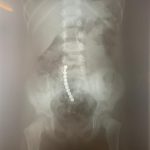

Dr. Adriana Constantineanu, medic specialist în chirurgie pediatrică atrage atenția asupra pericolului din spatele jucăriilor cu magnet. Acestea îi pot distra pe copii și pot fi fascinați de multitudinea de culori vii care îi duce cu gândul pe cei mici la bomboane, înghițindu-le.

Acești magneți sunt foarte puternici, iar ingestia lor poate duce la probleme gastrointestinale grave. Odată înghițiți sunt atrași unul spre altul chiar dacă se găsesc în secțiuni diferite ale tubului digestiv. O ansă intestinală prinsă între acești magneți se poate perfora ducând la tratament chirurgical de urgență. În secția noastră, de la începutul anului s-au prezentat trei cazuri, două fete și un băiat, cu vârste cuprinse între 2 și 4 ani. Aceștia au suferit perforații la nivelul intestinului subțire și au necesitat intervenții pentru îndepartarea porțiunii de intestin afectate”, a precizat dr. Adriana Constantineanu.